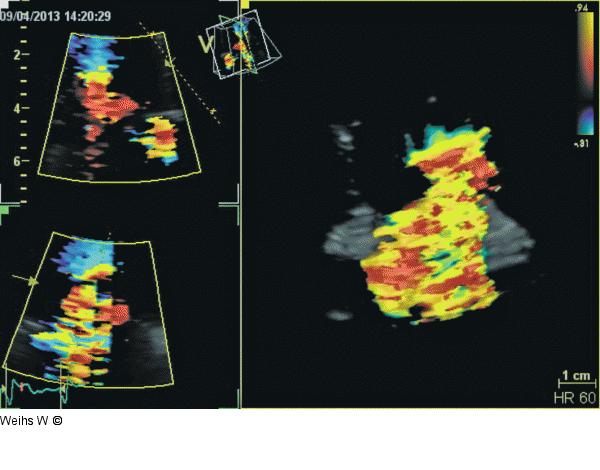

Abbildung 5: Trikuspidalinsuffizienz Dreidimensionale Darstellung der Trikuspidalinsuffizienz. Die Konvergenzzone, die Vena contracta und der Jet sind eindeutig abzugrenzen. |

Dreidimensionale Darstellung der Trikuspidalinsuffizienz. Die Konvergenzzone, die Vena contracta und der Jet sind eindeutig abzugrenzen. |